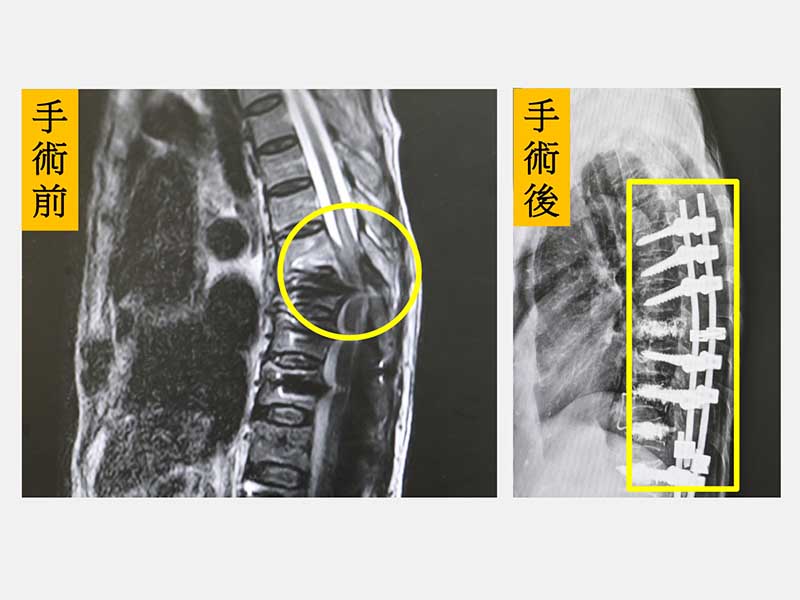

高齡陳老太太之前因為退化性脊椎側彎併脊椎狹窄症接受脊椎矯正、減壓和固定融合手術,手術後恢復得不錯,很快就回到正常生活。陳老太太有一天在家整理盆栽搬動花盆時突然背部一陣劇痛,下半身突然無力跌坐在地上,兩個下肢癱瘓無力,家人趕緊將她送到仁愛長庚合作聯盟醫院(大里仁愛醫院)的急診室。急診醫師發現陳老太太的大小腿癱瘓無力,只剩腳踝可微動,經過緊急核磁共振攝影檢查顯示第七胸椎發生爆裂性骨折,而且壓迫到脊髓,立即聯絡脊椎中心陳盈佑主任安排緊急手術,隔天其大腿開始有微微移動。陳老太太除了接受骨質疏鬆症的治療之外,在疼痛減輕後,復健科醫師安排復健療程積極訓練,約一個月後已經可以持著四腳助行器慢慢行走,逐漸正常生活。

陳盈佑主任指出,過去脊椎長節手術常運用在青少年自發性脊椎側彎及僵直性脊椎炎駝背畸形的病人,不過,近年來因為脊椎手術及醫療科技的進步,脊椎長節手術對老年病人已經不是禁忌。高齡病人可能因為退化性駝背、側彎或是因為脊椎骨折所導致的駝背畸形,需要接受脊椎長節手術來矯正,在超高齡社會的台灣,這類需要手術的病人逐漸增加。脊椎長節固定處常位於胸腰椎交界或胸椎中下段,由於交界處要承受上半身的重量,而且高齡長者會有骨質疏鬆,如果跌倒或姿勢不當就可能導致交界處骨折,輕則是單純的壓迫性骨折,嚴重則爆裂性骨折壓迫脊髓致下半身癱瘓。